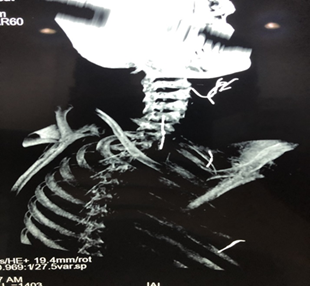

A cervico-thoracic CT-scan was done objectifying, in addition to multiple

subcutaneous metallic foreign bodies (Figure

2), a metallic wire which has migrated in the supra clavicular area and

reached the carotid region, between the internal carotid artery and the

internal jugular vein and reaching the upper part of the thorax, measuring

approximately 4cm (Figure 3).

Figure

3: Cervical CT-scan –

cross section showing cervico-thoracic steel wires embedded between the

internal carotid artery and the internal jugular vein